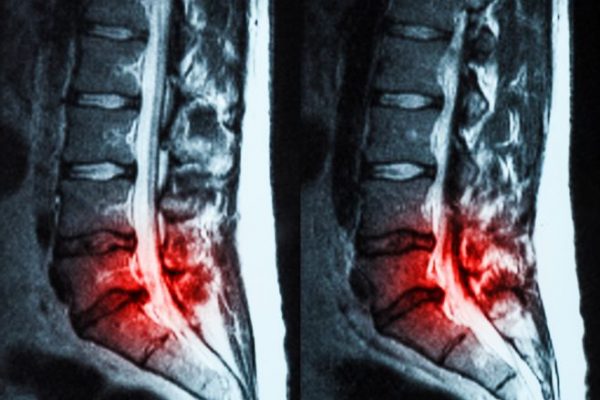

Tratamiento Quiropráctico para Hernias Discales

Las hernias discales pueden afectar tu calidad de vida, pero la quiropráctica ofrece una solución…

Alivio de Hernia Discal en Canovellas con Quiropráctica

Descubre cómo la quiropráctica puede ser una solución efectiva para la hernia discal. En el…